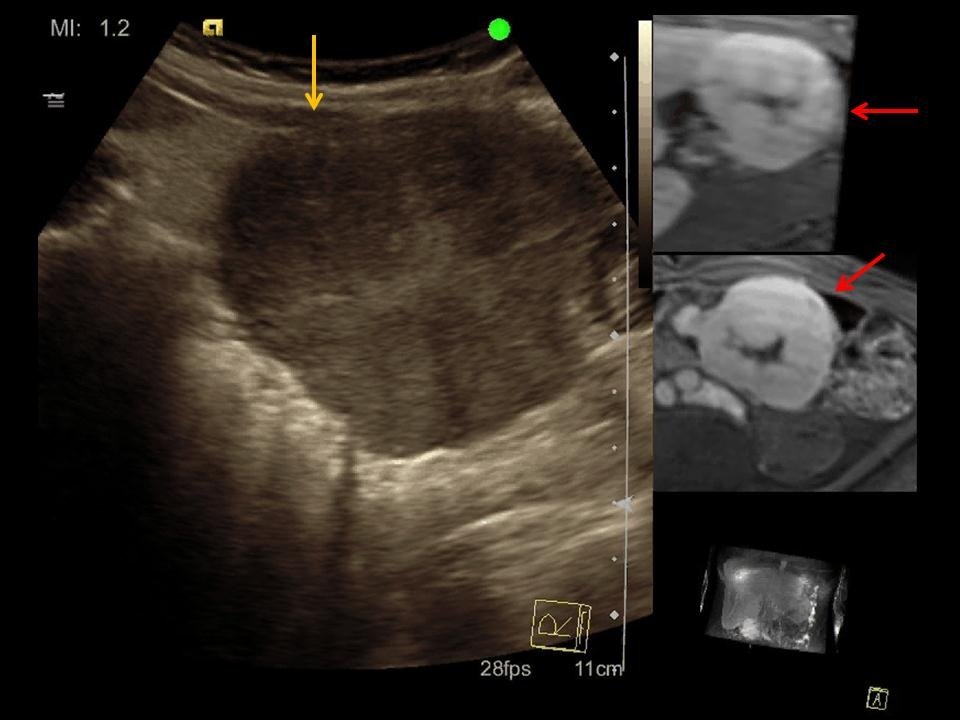

Magenkrebs und Ultraschall: Was ist möglich?

Die Frage, ob Magenkrebs im Ultraschall sichtbar ist, lässt sich nicht pauschal beantworten. Grundsätzlich ist der Ultraschall nicht die erste Wahl zur Diagnose von Magenkrebs. Die Magenschleimhaut und die tieferen Schichten des Magens sind durch die Luft im Magen und die darüber liegenden Organe schwer einsehbar.

Dennoch kann der Ultraschall in bestimmten Fällen Hinweise auf Magenkrebs liefern:

- Große Tumoren: Sehr große Tumoren, die die Magenwand verdicken oder in benachbarte Organe einwachsen, können manchmal im Ultraschall erkannt werden.

- Metastasen: Wenn der Krebs bereits Metastasen (Tochtergeschwulste) in anderen Organen, wie z.B. der Leber, gebildet hat, können diese im Ultraschall sichtbar sein.

- Aszites: Bei fortgeschrittenem Magenkrebs kann es zu einer Ansammlung von Flüssigkeit im Bauchraum (Aszites) kommen. Diese Flüssigkeit lässt sich gut im Ultraschall darstellen und kann ein indirekter Hinweis auf eine Krebserkrankung sein.

Allerdings gilt: Ein unauffälliger Ultraschall schließt Magenkrebs nicht aus. Kleine Tumoren oder Tumoren, die sich in den tieferen Schichten der Magenwand befinden, werden oft übersehen. Eine abschließende Diagnose kann in der Regel nur durch andere Untersuchungsmethoden gestellt werden.